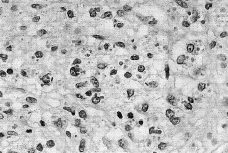

Tras punción-aspiración orientativa se realizó biopsia de la masa torácica, observándose una abundante celularidad atípica dispuesta en sábana, principalmente en dermis profunda e hipodermis, de hábito plasmocelular, constituidas por células de núcleos generalmente excéntricos, redondeados, grandes, con uno o dos nucléolos prominentes y mostrando un citoplasma finamente granular de frecuente disposición en babero y aisladamente células plasmáticas maduras entre la celularidad blástica (Fig. 2). El estudio inmunohistoquímico mostró una infiltración lambda monoclonal sugestiva de mieloma.

FIG. 2.--Infiltrado monomorfo difuso de células plasmáticas de specto blástico.